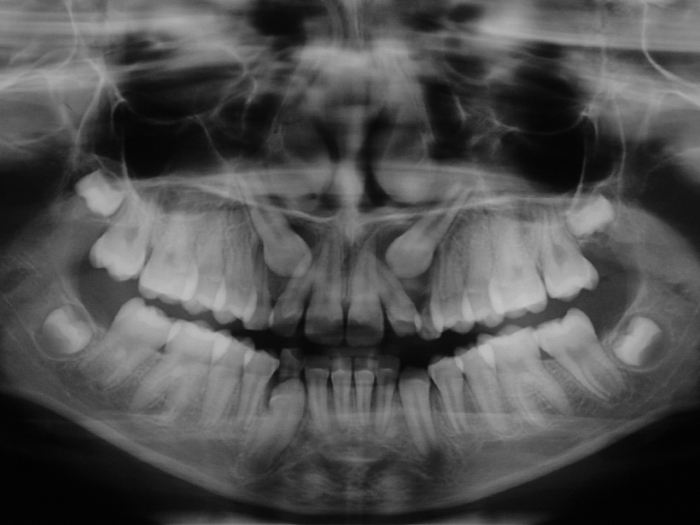

Rx Panorâmica inicial - 2014

Rx Panorâmica - 2018, com os caninos em posição